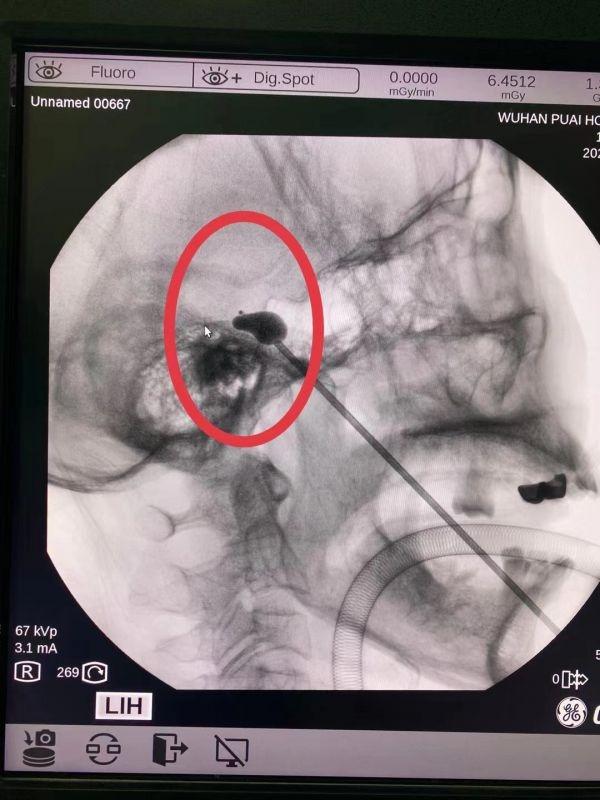

医生在患者三叉神经根部植入“梨子”状微球囊 。

根据张先生的病情 , 医生为其制定了“三叉神经痛微球囊压迫术”的手术方案 。 术中 , 华雷医生在C臂X光机的引导下 , 用一细针在患者左侧嘴角外精准穿刺到颅底卵圆孔 , 将微球囊送到目标位置 , 然后缓慢向微球囊注入造影剂 。 随着微球囊缓慢涨起 , 在X光透视下呈现标准的“梨子”形状 。 压迫3分钟后 , 手术医生拔出微球囊导管及穿刺针 , 手术从麻醉到结束用时不到1小时 。 术后 , 折磨张先生十余年的疼痛终于消失 。